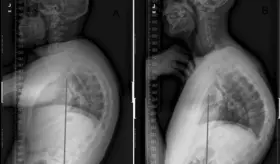

-La hipercifosis, cuando la curvatura de la columna supera los 40 grados, puede estar asociada con fracturas vertebrales, especialmente en adultos mayores, afectando la movilidad y la calidad de vida.